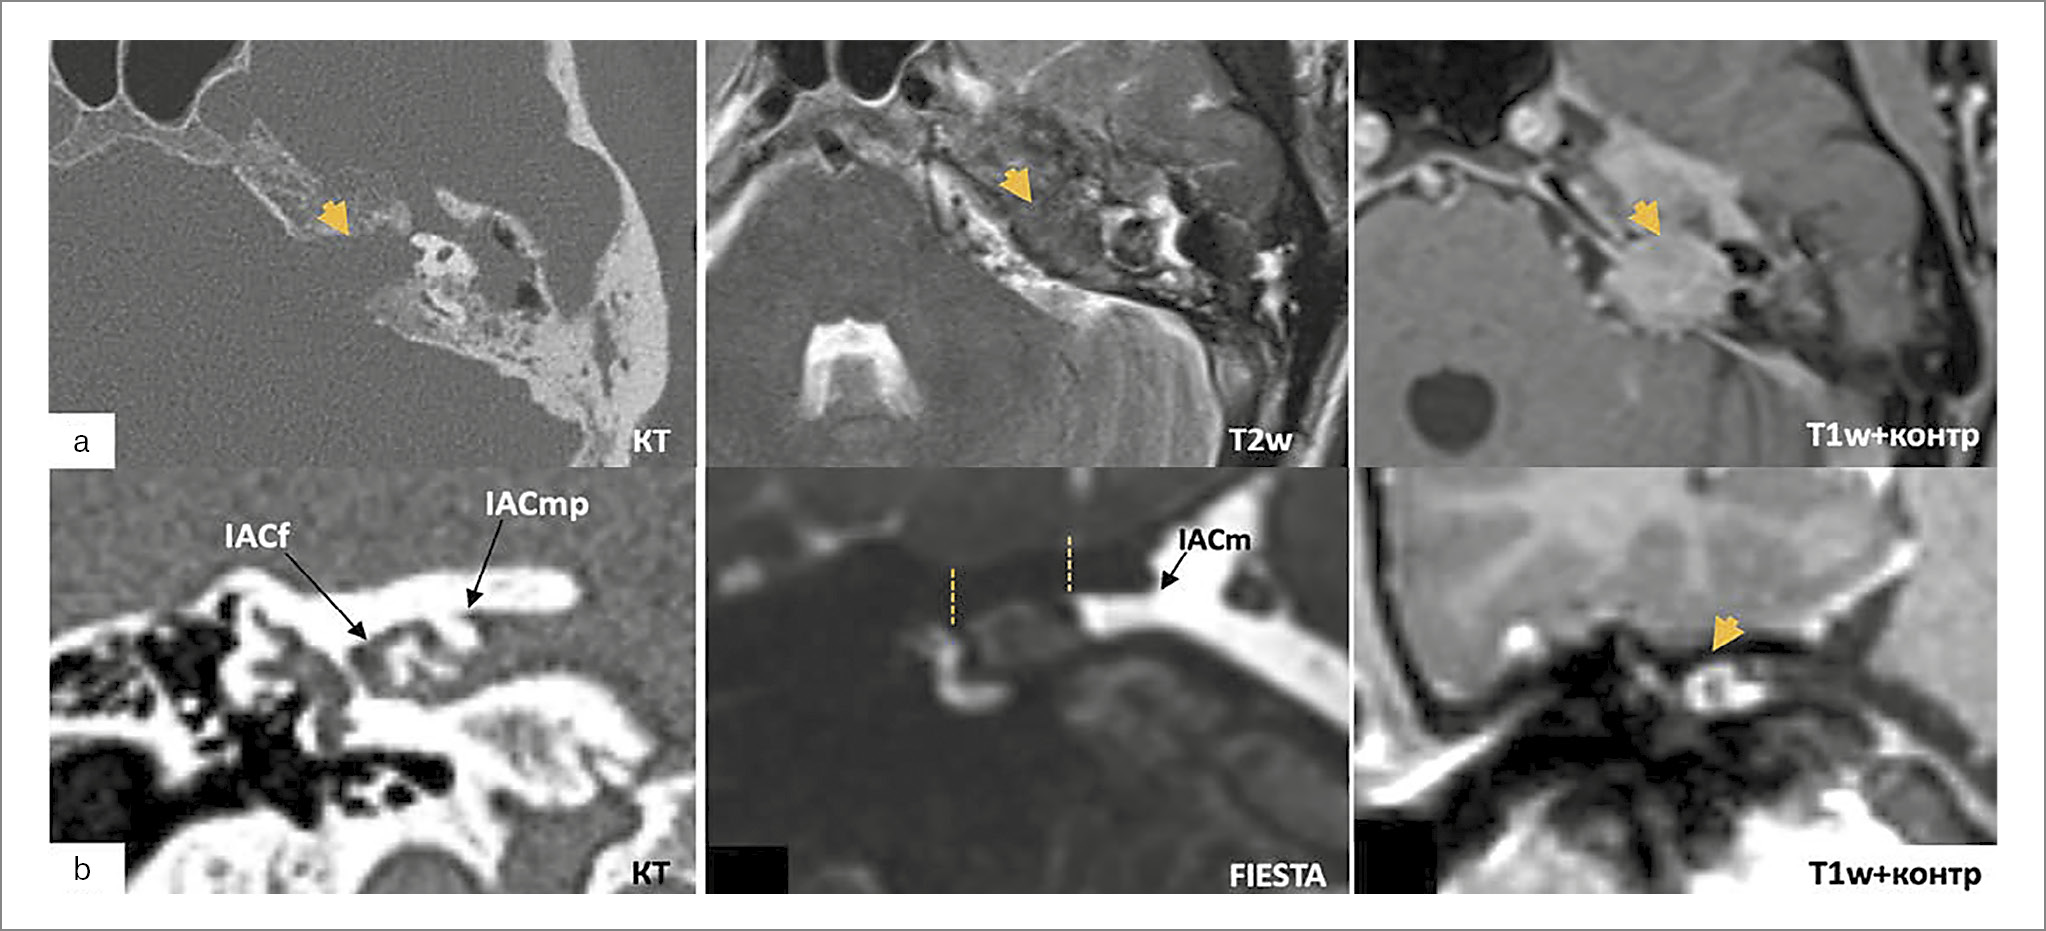

Тимпаноюгулярная параганглиома – вторая по частоте опухоль височной кости и самая распространенная опухоль, поражающая яремное отверстие, которая чаще встречается у европеоидов (преимущественно женского пола) с пиком в 5 и 6-м десятилетиях жизни. Опухоль характеризуется медленным ростом, инвазией костей основания черепа, инфильтрацией нижних ЧМН и вовлечением в процесс крупных кровеносных сосудов: луковицы яремной вены, внутренней сонной артерии, сигмовидного синуса, позвоночной артерии [51]. Поражение ВСП и интракраниальное распространение параганглиомы встречается редко и преимущественно бывает при тимпаноюгулярной и вагальной формах. Гистологически параганглиомы состоят из эпителиоидных однородных главных клеток и поддерживающих клеток, обычно образующих кластеры. Иммуногистохимически эпителиоидные главные клетки экспрессируют синаптофизин и хромогранин, что активно используется для установки окончательного гистологического диагноза. Для определения распространения роста широко принята классификация Fisch (1988 г.) в модификации S. Sivalingam и M. Sanna (2012 г.), базирующаяся на данных исследований КТ и МРТ [52]. По данным КТ, характерный признак – выраженное разрушение височной кости (каналов внутренней сонной артерии, луковицы яремной вены, сигмовидного синуса, ЛН); по МРТ в Т1-режиме изоинтенсивна; Т2 неоднородна (преимущественно изоинтенсивна с гипер- и гипоинтенсивными включениями – симптом «соли и перца»), в Т1 с внутривенным контрастированием определяется выраженное накопление контрастного вещества. Интрадуральное распространение, включающее себя пространство ВСП, обозначается буквой D. Опухоль обычно распространяется в субарахноидальное пространство, проникая в твердую мозговую оболочку ЗЧЯ вдоль нижних ЧМН (рис. 4). Однако описаны случаи интрадурального роста опухоли через ВСП и твердую мозговую оболочку средней ямки [53, 54]. По данным M. Sanna и соавт., в некоторых случаях не исключено распространение параганглиомы в ММУ и кавернозный синус непосредственно из-за инвазии ПВК. Большинство случаев Di1 были С2 (59,2%), а случаи Di2 были С3 (72,2%). Это показывает, что степень интрадурального вовлечения коррелирует с ростом класса опухоли [53].

Рис. 4. Исследования пациентов с параганглиомой и остеомой ВСП: а – параганглиома с распространением в ВСП; b – интраканальная остеома ВСП. IACf – дно внутреннего слухового прохода; IACmp – средняя часть внутреннего слухового прохода; IACm – внутреннее отверстие внутреннего слухового прохода.

Остеомы и экзостозы ВСП

Костные поражения ВСП встречаются редко и в основном протекают бессимптомно. Различные костные патологии ВСП, приводящие к стенозу его просвета, чаще являются следствием генерализованных поражений костной ткани: фиброзной дисплазии, болезни Педжета, гигантоклеточной опухоли кости, отеобластомы, остеита ПВК. Встречаются только 2 типа солитарных доброкачественных образований: остеома и экзостоз [55, 56]. Дифференциация остеом и экзостозов ВСП может быть сложной задачей. Остеома представляет собой тип медленнорастущей доброкачественной опухоли кости, которая обычно диагностируется в наружном слуховом проходе [55, 57]. Остеомы имеют более тонкую ножку и характеризуются фиброваскулярными каналами, окруженными неравномерно ориентированной пластинчатой костью. Напротив, экзостозы обычно представляют собой возвышения кости с широким основанием, состоящие из параллельных слоев поднадкостницы [57, 58].

Первое описание остеомы ВСП было сделано V. Singh и соавт. в 1992 г. [59]. V. Gerganov и соавт. описали первый случай двусторонней остеомы ВСП [59]. Всего в зарубежной литературе выявлено 26 клинических случаев остеомы ВСП, при этом нет ни одного исследования ее происхождения. Точная причина возникновения остеом не установлена, имеются несколько возможных этиологий развития: травма, инфекция, воспаление, контакт/раздражение от прилежащих кровеносных сосудов, гормональные или генетические факторы или участки различного эмбриологического происхождения [60].

В большинстве случаев остеома ВСП – рентгенологическая находка [55, 61]. Диагноз устанавливают преимущественно на основании тонкосрезовой (0,5–0,7 мм) КТ, где определяется гомогенная опухоль кости на ножке, хорошо ограниченная, округлая или многодольчатая [62]. При анализе существующих публикаций точная локализация остеомы в ВСП (дно, средний отдел, внутреннее отверстие) и стенка ее происхождения (передняя/верхняя/задняя/нижняя) отмечены не во всех рассмотренных исследованиях, что может быть важно для понимания преобладания тех или иных клинических симптомов. J. Vrabec и соавт. указали, что в 6 случаях из 7 остеома выявлена в латеральных отделах ВСП [62]. По МРТ-исследованию возможно ошибочно диагностировать остеому с ВШ из-за плохой визуализации опухоли в стандартных режимах из-за ее малых размеров [63]. Последовательность FIESTA полезна для обнаружения небольших поражений ВСП, но для исключения костных опухолей следует выполнять КТ-исследование височной кости.

Клинические симптомы остеомы вариабельны, несмотря на сходные рентгенологические данные (снижение слуха от незначительного до глубокого; шум в ушах от периодического до постоянного); вестибулярные расстройства варьировали от позиционного до постоянного головокружения [63]. В литературе не описано случаев дисфункции мимической мускулатуры на фоне остеомы ВСП [64]. Нечастое поражение ЛН может быть связано с преимущественной локализацией образования по нижней и задней стенкам ВСП, что делает степень компрессии лицевого ствола не столь значительной. В 2010 г. B. Lietin и соавт. описали пациента с гемифациальным спазмом как первым проявлением [61].